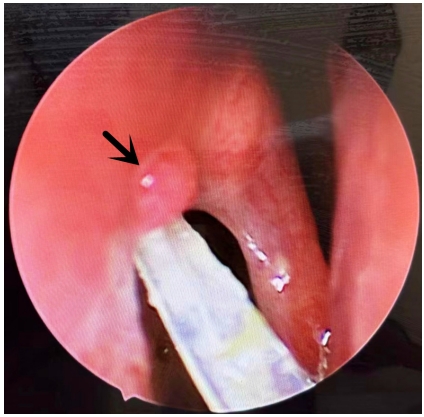

手术方法:术中沿中鼻甲前缘附着点上方约8 mm处做弧形切口,形成一约1 cm × 1.2 cm黏膜瓣,钝性分离至泪颌缝,以泪颌缝为标志,用美敦力(Medtronic,美国)IPC刨削动力系统粗磨,咬除上颌骨颈突,造一直径为1 cm大小的骨孔,暴露泪囊,经上泪小点置入探针,撑起泪囊壁,近上缘弧形切开泪囊内侧壁,形成一黏膜瓣,开放前组筛窦,剪开鼻黏膜瓣,使其贴附于泪囊造口周边骨面上,泪囊瓣与鼻黏膜瓣之间无需缝合,周围填充沾有妥布霉素地塞米松眼膏眼药膏的吸收性明胶海绵[14],见瘘口形成良好,检查无出血。合并泪总管、泪小管狭窄时植入泪道引流管,分别自上下泪小点插入引流管,自鼻腔内勾出并打结。术中同期处理鼻腔、鼻窦病变。手术均由同一位经验丰富技术熟练的医师完成。术后随访及处理:术后1个月内用药为布地奈德鼻喷雾剂2次/天,0.1%氟米龙滴眼液滴术眼3次/天。术后每2周复查1次鼻内镜检查,复查3次后根据恢复情况确定随访间隔时间,所有患者随访时间均大于6个月。随访内容包括以下3项:1)鼻内镜下鼻腔处理,清除鼻腔内血痂、分泌物、黏膜粘连及增生的肉芽组织,如发现肉芽组织增生(图1、3),则用枪镊夹除肉芽组织,造瘘口周围涂妥布霉素地塞米松眼膏,其中物理清除联合TA组予鼻黏膜下注射TA注射液(40 mg/mL)0.3 ~ 0.5 mL,保证注射面积覆盖80%肉芽组织创面(图2、4),间隔2周复查,如发现肉芽复发则再次清除并注射TA。2)泪道冲洗,分别经上下泪小点以地塞米松注射液和生理盐水冲洗泪道。3)如术中联合植入泪道引流管,一般于3个月后拔除。

图1 造瘘口肉芽组织增生

Figure 1 Granuloma formation in the ostium